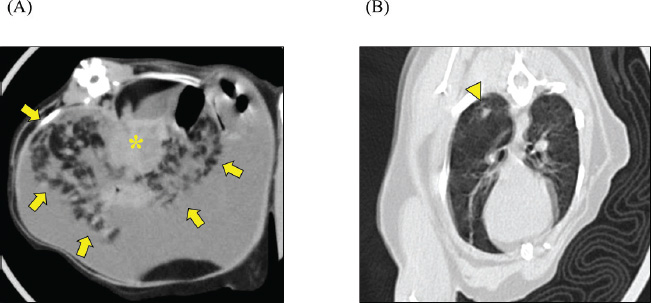

A 2-year-old castrated male domestic shorthair cat, weighing 5.3 kg, presented with a 2-month history of abdominal distension and a 4-day history of anorexia. There was no history of illness or abdominal surgery. Physical examination revealed severe abdominal distension with a fluid wave and mild hypothermia (37.1°C). Blood tests revealed mild elevations in blood glucose (178 mg/dl; reference interval 71–148 mg/dl) and serum amyloid A (5.27 µg/ml; reference interval <3.75 µg/ml) levels, while lipase activity was within normal limits (23.9 U/l; reference interval <30 U/l). Abdominal radiography revealed increased radiopacity and digestive tract consolidation (Fig. 1). Abdominal ultrasonography revealed severe ascites, small intestine hypoperistalsis, pancreatic enlargement, and irregular thickening of the peritoneum with several nodules (Fig. 2). Echocardiography revealed no abnormality. In the ascitic fluid analysis, the total nucleated cell count was 1,000 cells/μl with no evidence of neoplastic cells or bacterial infection, and the specific gravity of the supernatant was 1.024, confirming the ascites as a modified transudate (Fig. 3). Feline infectious peritonitis was considered unlikely due to the absence of feline coronavirus genes in the ascitic fluid and no elevation in blood anti-coronavirus antibody titers. Based on the imaging findings, such as peritoneal thickening, gastrointestinal tract consolidation, and severe ascites, EPS was initially suspected. These findings are consistent with the typical presentation of EPS, characterized by fibrotic thickening of the peritoneum and encasement of abdominal organs (Gremillet et al., 2022). However, the possibility of malignancy was deemed unlikely due to the cat’s relatively young age. A trial treatment with prednisolone (10 mg/head, q24 h) and enrofloxacin (25 mg/head, q24 h) was initiated to manage the suspected inflammatory process and potential bacterial infection, respectively. However, no clinical improvement was observed, suggesting that the underlying condition might be more complex than initially suspected. A non-sedated computed tomography (CT) scan was performed to obtain more detailed diagnostic information on day 12 after presentation. A Siwtenn-slice multi-slice CT scanner (Aquilion™ Lightning, Canon Medical Systems, Japan) was used without anesthesia, with the patient restrained in an acrylic cage (CT capsule, Terucom, Japan). The following technical parameters were used: rotation time=0.75 s; slice thickness=1 mm; reconstruction interval=0.5 mm; table speed=16 mm/rotation; helical pitch=16.0; X-ray tube voltage=120 kV; and X-ray tube current=100 mA. The CT scan revealed a tumor-like enlargement of the pancreas, irregular scattered nodular formations aggregating dorsally in the peritoneum, and ground-glass opacity in the right lower lobe of the lung (Fig. 4). Because angiography was not performed, the vascular characteristics and more detailed differentiation of the soft tissue masses could not be assessed. A pancreatic tumor was suspected; however, diagnostic and therapeutic surgical interventions were deemed difficult due to the animal’s condition. In addition, the owner declined further invasive procedures, such as fine-needle aspiration or laparoscopy. Despite prednisolone treatment (5 mg/head, 24 h), ascitic fluid drainage, and fluid therapy, the cat died 19 days after the first presentation.

Fig. 1. Abdominal radiographs. (A) Right lateral and (B) ventrodorsal radiographs are shown. The images show severe abdominal distension and a generalized decrease in contrast, suggesting ascites. Mild gas retention and clustering of the intestines were observed (arrow).